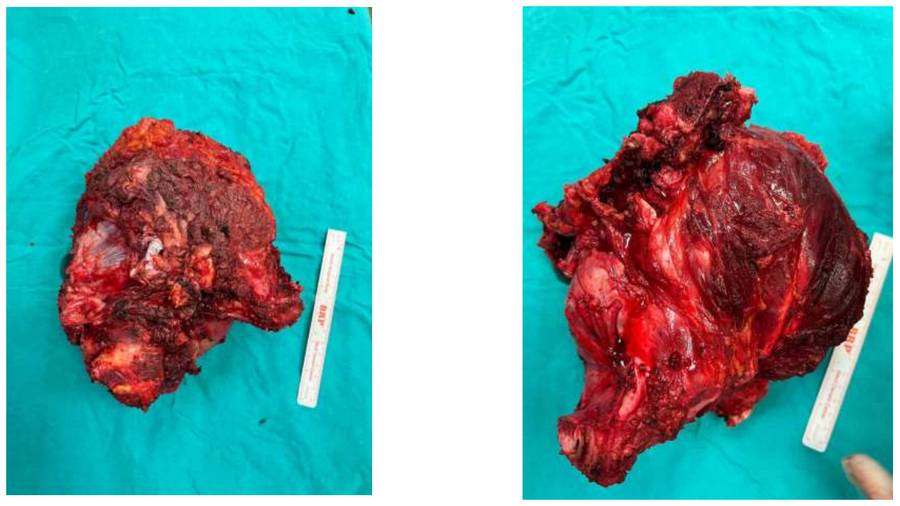

During the operation: Clinical image of the removed tumor tissue.